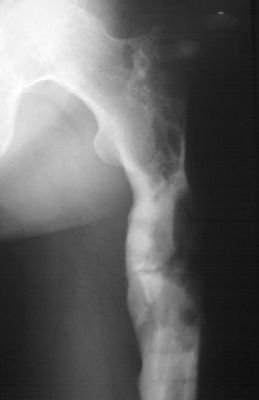

Уважаемые коллеги! Выношу на обсуждение клинический случай. Пациент 38 лет, оперирован дважды. В настоящее время рефрактура. Подробности из анамнеза: в 2007 году пациенту выполнена операция остеосинтез бедренной кости по поводу многооскольчатого перелома с применением пластинки с ограниченным контактом (имплантов с угловой стабильностью и блокируемых гвоздей на момент операции в наличии не было - это, чтобы не обсуждать лишние вопросы). Через 6,5 месяцев после остеосинтеза развился остеомиелит в верхней трети диафиза бедренной кости с образованием секвестра размерами 55х30х25 мм. В 2008 году (через 8 месяцев после остеосинтеза) выполнена вторая операция - удаление металлоконструкции и секвестрэктомия. При удалении пластинки и ревизии ложа секвестра, костная мозоль на сросшемся участке состоятельна. было принято решение заполнить секвестральную полость мышечным лоскутом. В послеоперационном периоде нагрузка на конечность была исключена 2,5 месяца, дополнительная фиксация индивидуальным брейсом. Свищи зажили, обострения остемиелита купировано. Пациент приступил к профессиональной деятельности (автослесарь). В конце ноября при уборке снега произвел резкую опорную нагрузку на конечность, после чего появились умеренные боли нарастающие в течение месяца. В настоящее время госптализирован для оперативного лечения по поводу рефрактуры на уровне верхней трети бедренной кости. Планируется остеосинтез аппаратом Илизарова с стержневой модификации (без обширного вмешательства в зоне перелома)и как вариант тунеллизации через зону перелома с возможным введением в каналы "КоллапАнна", "Сhronos" и.т.п. Также были предложены варианты пластинками с угловой стабильностью, блокируемый остеосинтез гвоздями. Движения в коленном суставе до повторного перелома (сгибание 90 градусов, разгибание 180). Пациент пониженного питания. Какие есть мнения по решению данного случая, может кто-то сталкивался с подобными вариантами развития событий. Всем заранее благодарен за Ваше время. Михаил.

Мне кажется, такой диагноз не отражает всей проблемы. Тут есть и значительный краевой дефект.